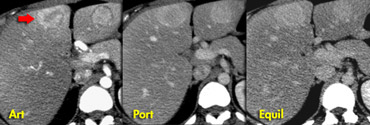

Typical hemangioma with nodular peripheral enhancement. Typical hemangioma with nodular peripheral enhancement.

Enhancement in Hemangioma

A hemangioma is a slowly perfused vascular space.

So the timing and amount of enhancement will follow, but lag behind the arterial system.

Hemangiomas less than 1 cm frequently demonstrate immediate homogenous enhancement, isodense to the aorta.

Hemangiomas larger than 1cm generally show slow centripetal spread of nodular enhancement, slowly decreasing in density.

On the left a typical hemangioma.

Enhancement in arterial phase is almost isodense to the aorta, and, as contrast diffuses toward the center of the lesion, the level of enhancement lowers slowly, and in the late phase is still hyperdense compared to the vascular spaces.